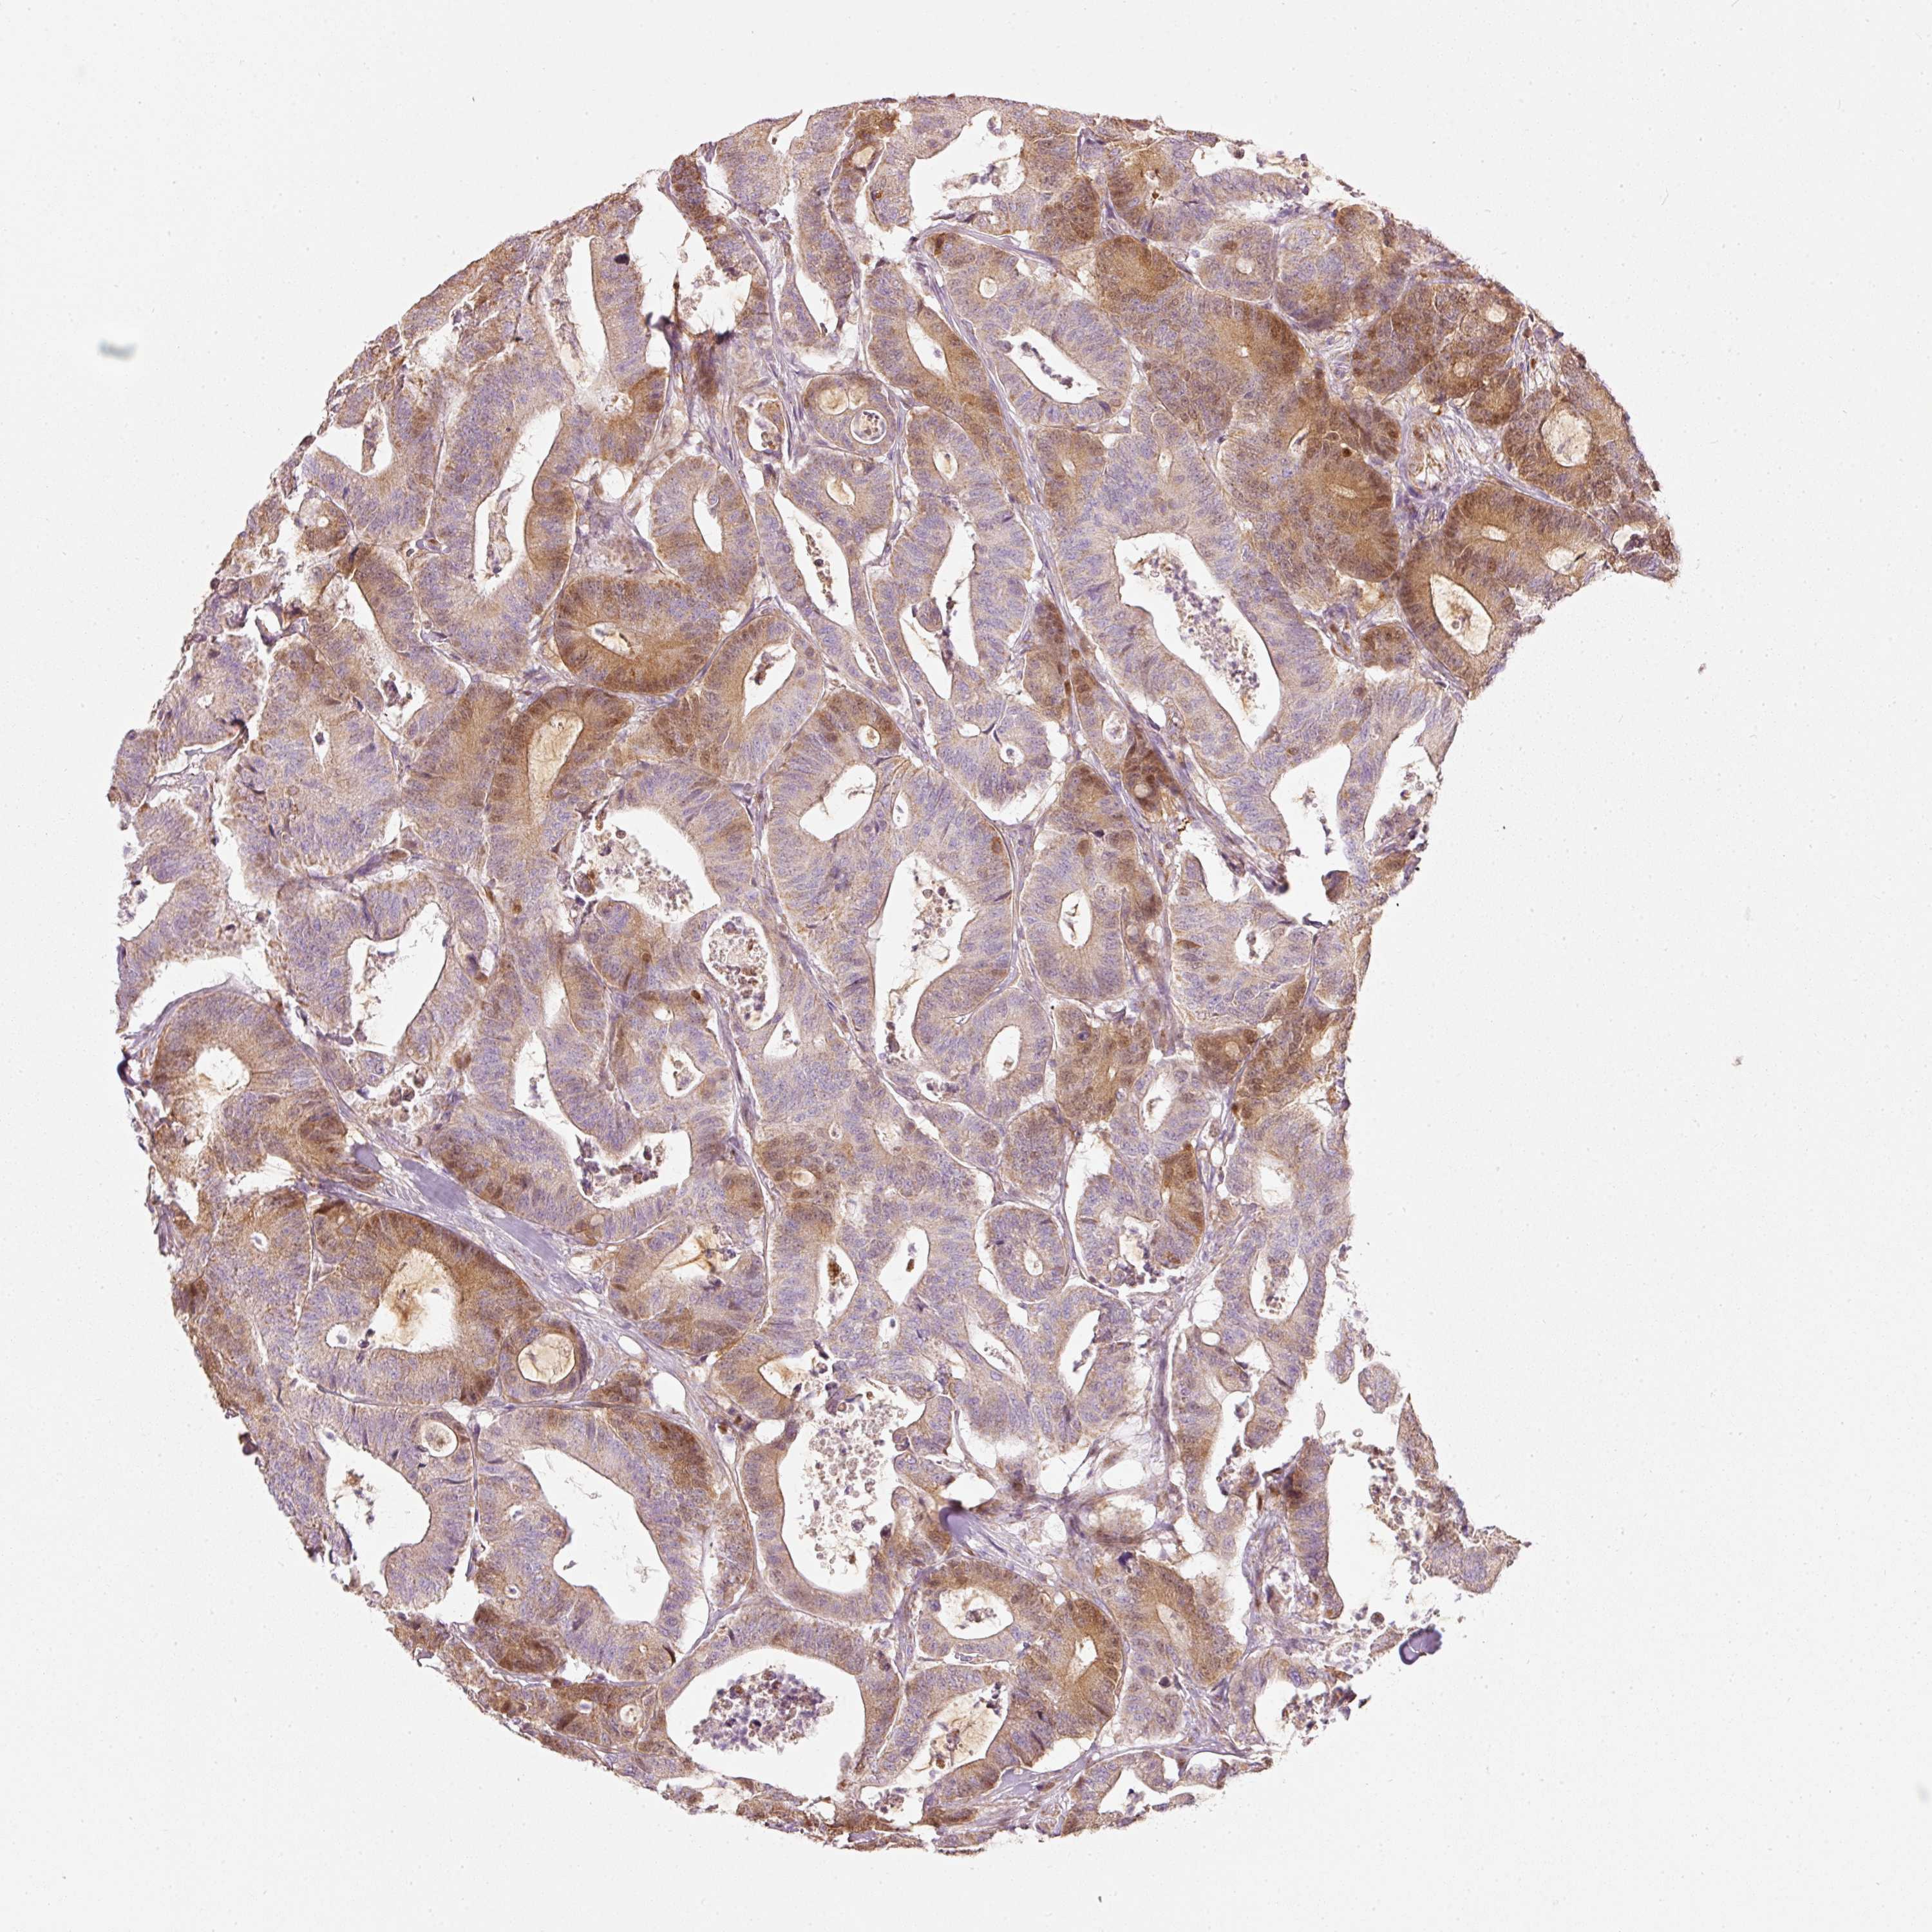

CANCER COLORECTAL CANCER Show tissue menu

COAD TCGA COAD VALIDATION READ TCGA READ VALIDATION PROTEIN COAD CPTAC PROTEIN EXPRESSION

Colorectal cancer

Human cancer

Colon adenocarcinoma